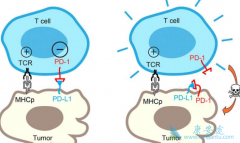

PD-1抑制剂 纳武单抗 (Nivolumab)与CTLA4抑制剂伊匹单抗,可通过激活免疫系统以对抗癌症。既往研究提示两种单抗分别对肾细胞癌有效,并且在其他肿瘤治疗中两者联用比单用有效。舒尼替尼是血管内皮生长因子受体酪氨酸激酶抑制剂,为晚期肾细胞癌的一线 ...

纳武单抗 (Opdivo)是一种通过抑制细胞上PD-1蛋白的细胞通路而发挥作用。自2014年纳武单抗获批上市以来,其适应症也在不断增加,截至目前纳武单抗的适应症已经达到了8个。那纳武单抗的八个适应症分别是什么,在治疗这些疾病时用法用量都是怎样的呢?下边 ...

近几年,癌症治疗发生了天翻地覆的变化。以 PD-1抑制剂 为代表的癌症免疫疗法,正在逐渐成为癌症治疗的新希望。PD-1抑制剂在多个癌症治疗的临床实验中,都展现除了超过传统癌症疗法如化疗的疗效,是目前癌症治疗的领先治疗方案。 截止到目前,PD-1抗 ...